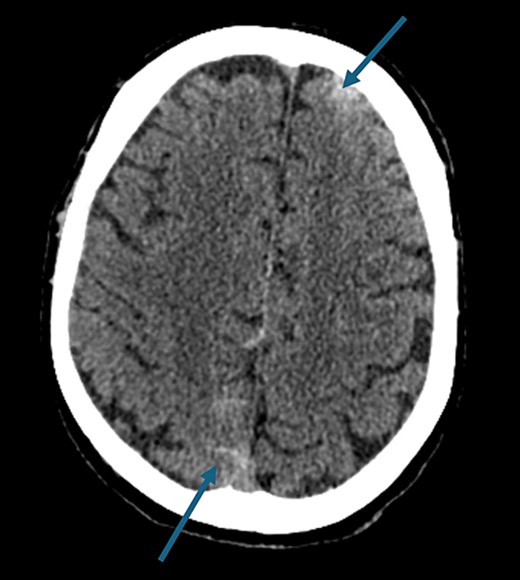

On presentation to the hospital, he was found to be in hypertensive crisis. Non-contrast head CT scan showed moderate volume biconvexity SAH (Fig. 1). CT angiography (CTA) of his head and neck showed a left internal carotid artery (ICA) dissection extending from the mid cervical segment to the level of the vertical petrous segment. Six vessel digital subtraction angiography confirmed a left ICA dissection extending from the proximal mid cervical ICA into the petrous segment. In the same region, there was also a left pseudoaneurysm formation with slight turbulent flow and stagnation (Fig. 2).

Non-contrast axial head computed tomography scan demonstrating biconvexity subarachnoid hemorrhage.